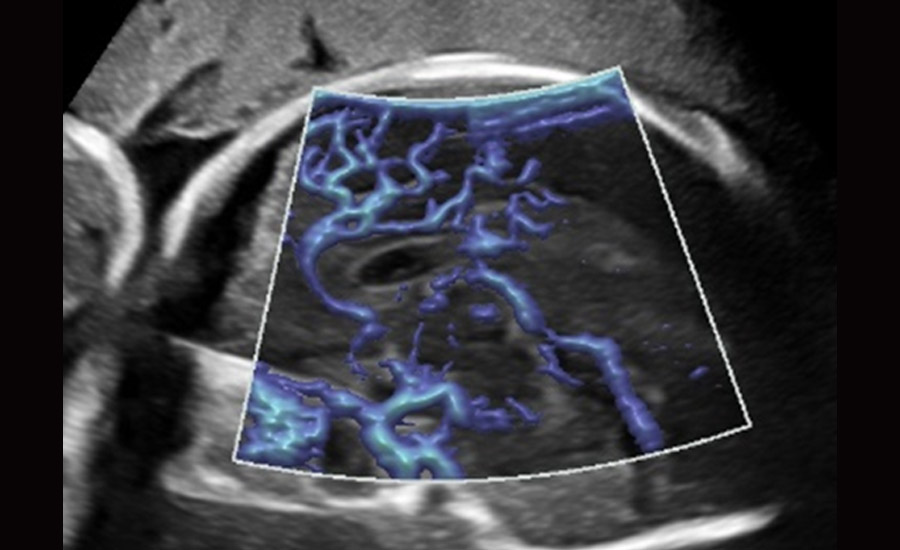

UMA (angiografia ultramicroscĆ³pica)

A tecnologia inovadora elimina as limita??es das tradicionais imagens com Doppler. Com resolu??o espacial e sensibilidade de fluxo ultra-altas, permite a detec??o de perfus?es de fluxos muito sutis e lentos, ampliando assim a aplica??o clĆnica da avalia??o qualitativa e quantitativa do ultrassom no cĆ©rebro fetal, rins, placentas, endomĆ©trios, ovĆ”rios etc.

UMA 3D ā Fluxo intracraniano do feto